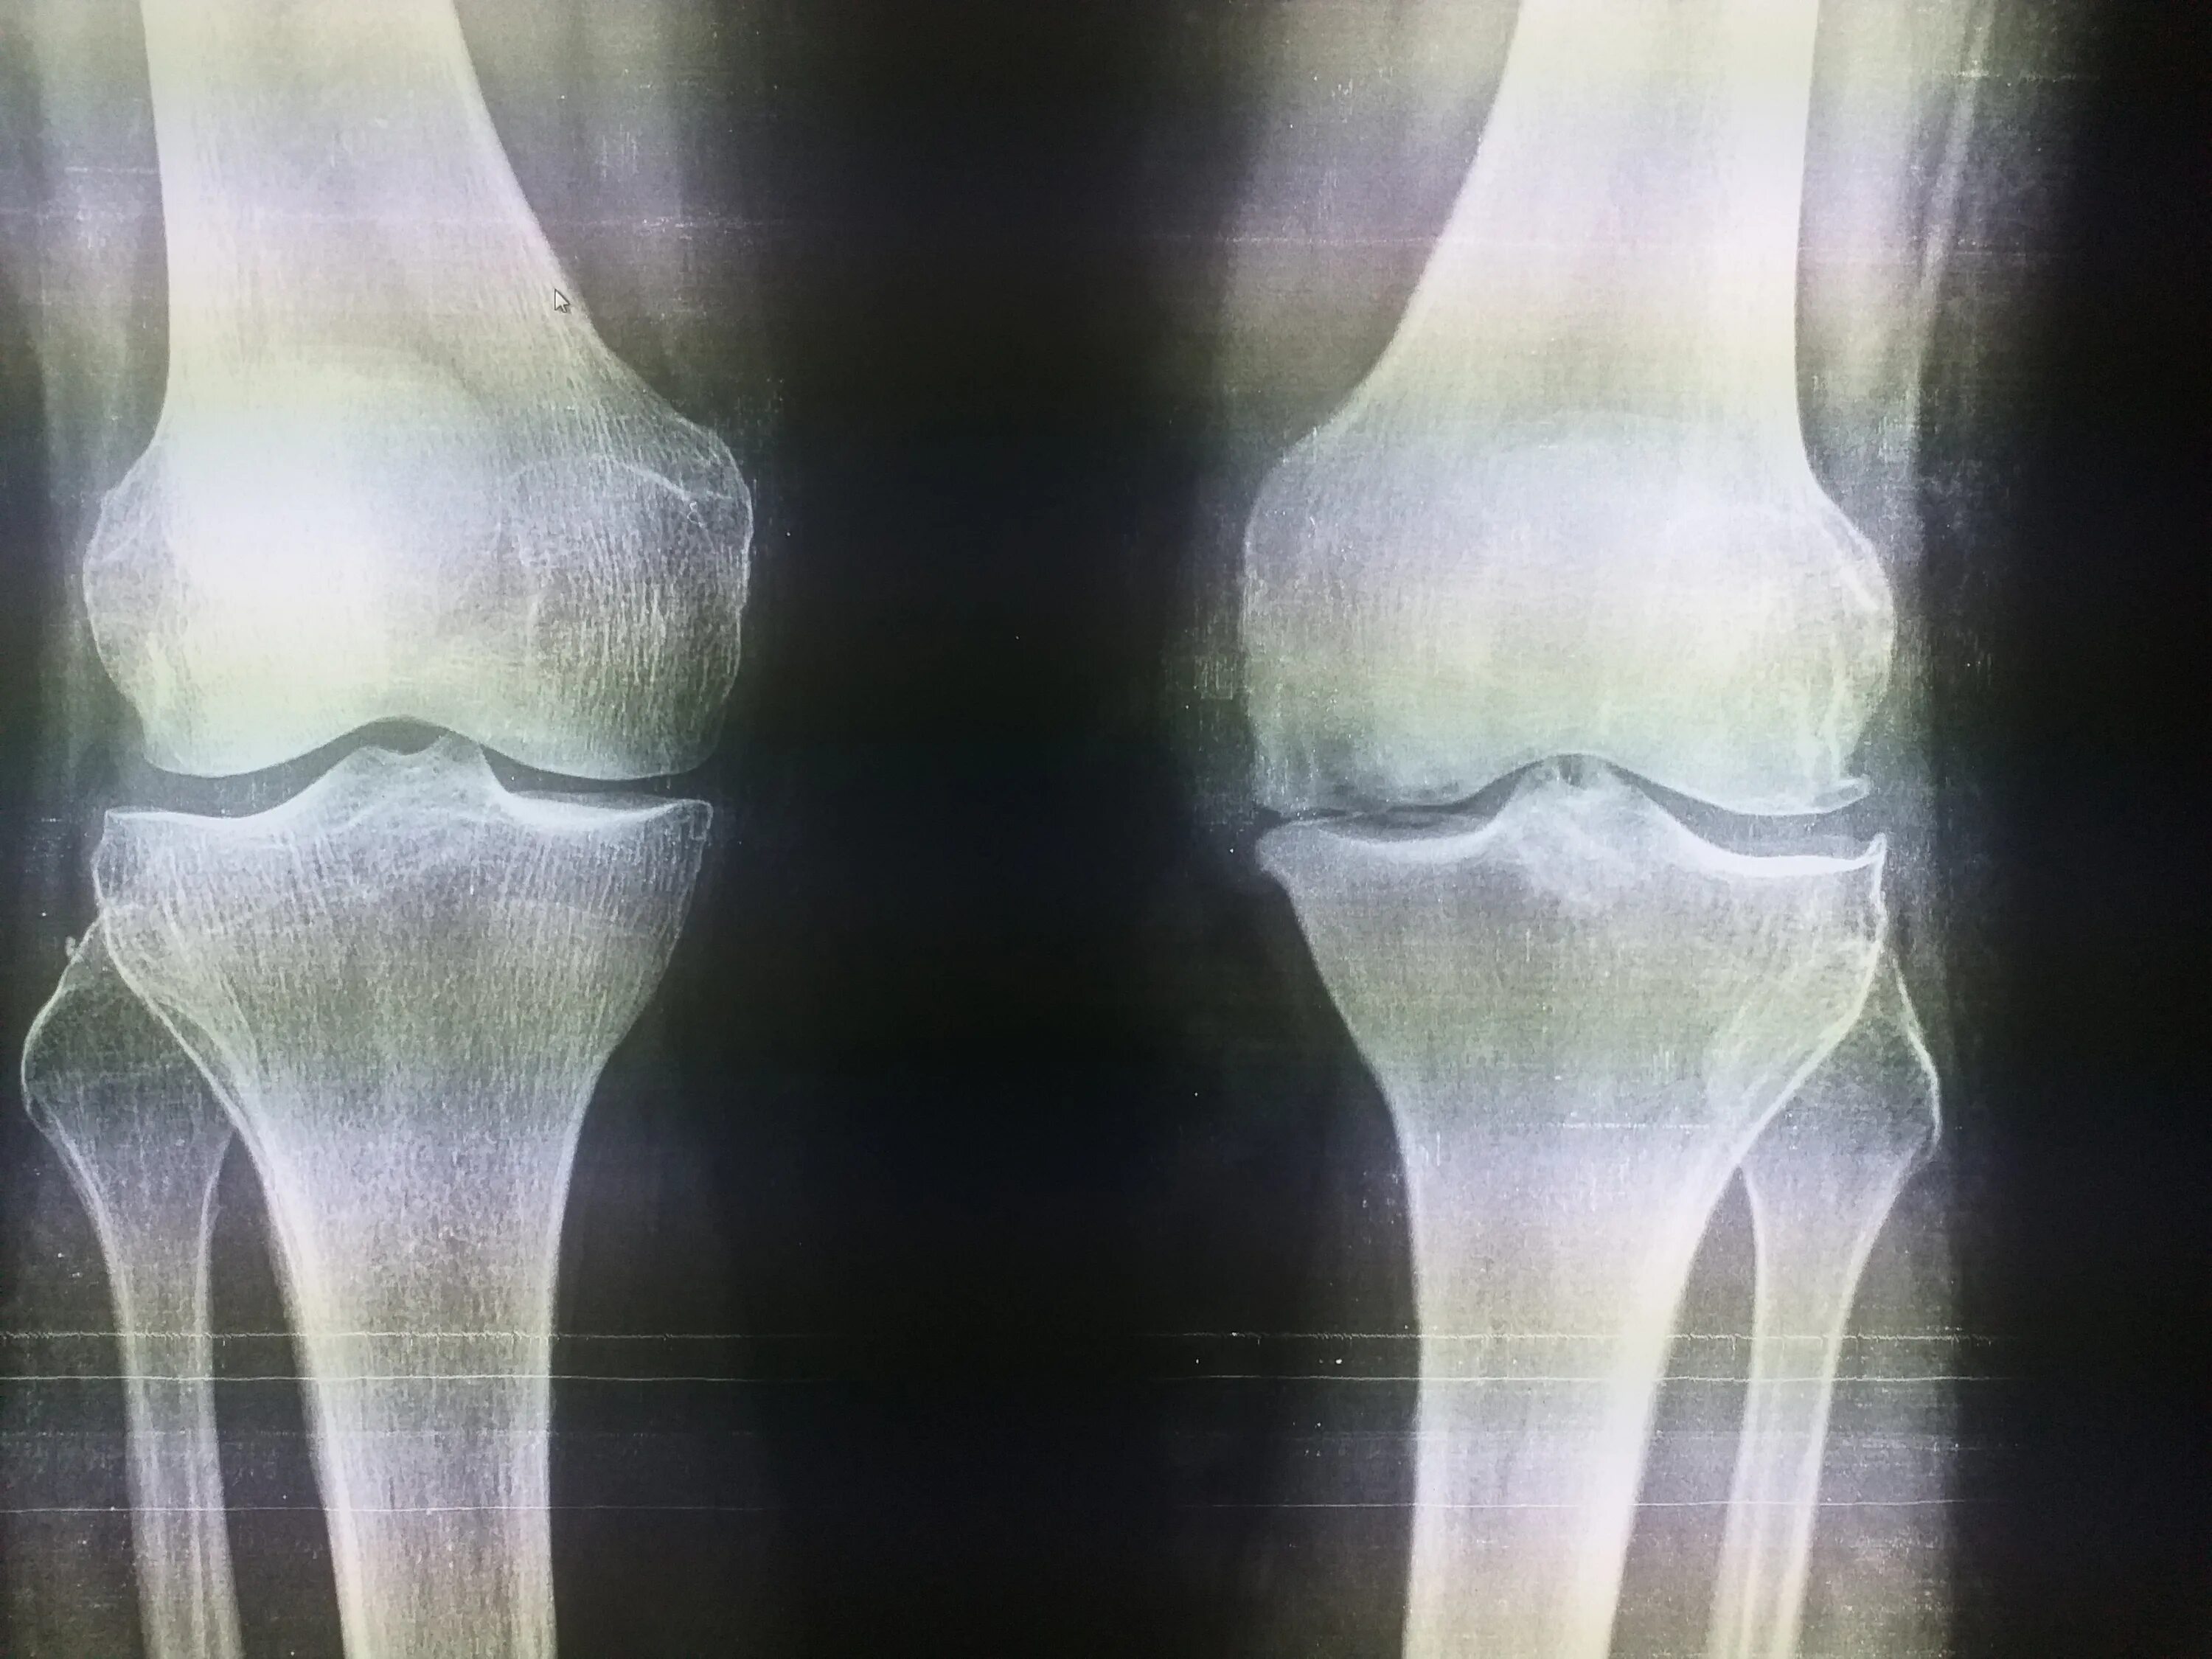

Келлера 3